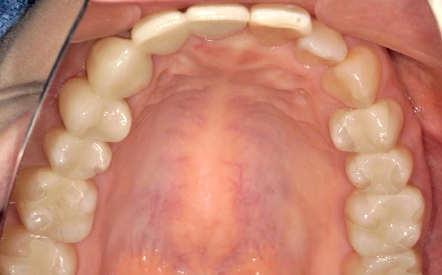

After

全顎的に不良補綴物(被せもの)を除去し、ジルコニアにて補綴物を新製。

全顎的に不良補綴物を外し、カリエス(虫歯)を除去。中心位(顎関節による決定する顎位)にて咬合採得を行い、ジルコニアにて修復を行いました。現在、咬合、機能、審美、ともに全く問題なく経過しています。